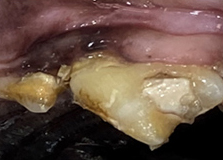

치근단 농양

Tooth root abscess

눈 주변 조직을 파괴하므로 조기 치료가 매우 중요합니다.

치근농양은 노출된 신경관에 세균이 감염되어 발생하며 주로 파절되거나 손상된 치아에 생기는데, 많은 경우 치주질환과 함께 연관되어 생기기도 합니다. 눈밑이 부어있거나 염증이 생긴 경우, 혹은 이 염증에서 고름이 나오는 경우나 이런증상이 반복되는 경우 강력히 의심해볼 수 있습니다.

치근농양을 방치할 경우 특히 눈 주변 조직을 파괴하므로 조기 치료가 매우 중요하며 전문적인 치과치료가 필수입니다.